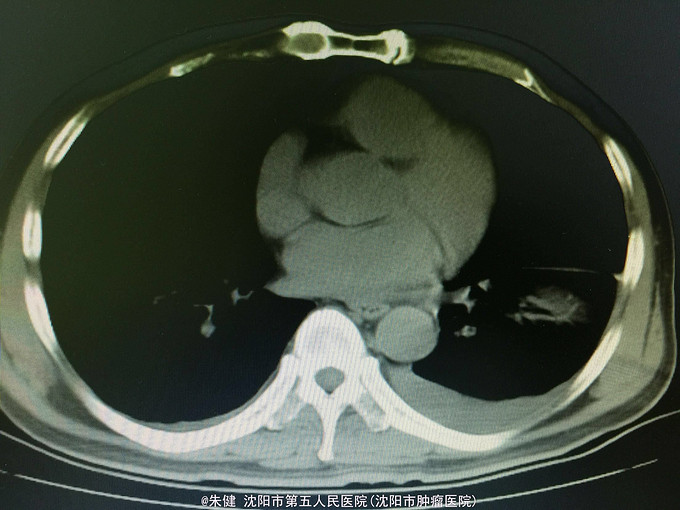

一般状态可,腹部平坦,未见肠形及蠕动波,剑突下及左侧上腹部压痛,轻度肌紧张,未及包块,无移动性浊音,肠音正常,肾区无扣痛。 辅助检查:血常规:白细胞13.6*10^9/L,中性83.3/L;尿淀粉酶:214U/L,上腹部CT:左侧胸腔积液,左肺下叶可见斑片及索条状影;胆囊增大,胆道内未及结石影;胰腺形态及密度正常,胰腺尾部周围可见索条状影及积液影。

诊断:急性胰腺炎 处理:给予禁食、补液、抗炎及抑肽酶治疗,病情逐渐好转,一周后出院。